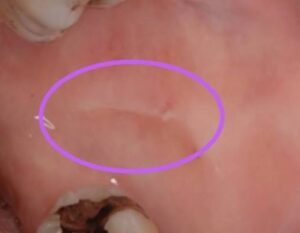

頬の内側に白い一本の線がある

これらは、無意識のうちに歯とベロ、あるいは歯と頬が強く押し付けられている証拠です。